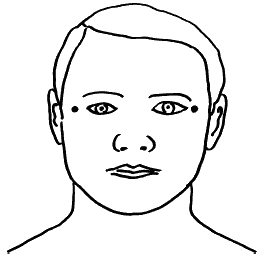

В целях профилактики можно с помощью второго человека или самим провести обследование щитовидной железы — аккуратно пальцами прощупать шею. Найдете хоть малейшее уплотнение — к врачу!